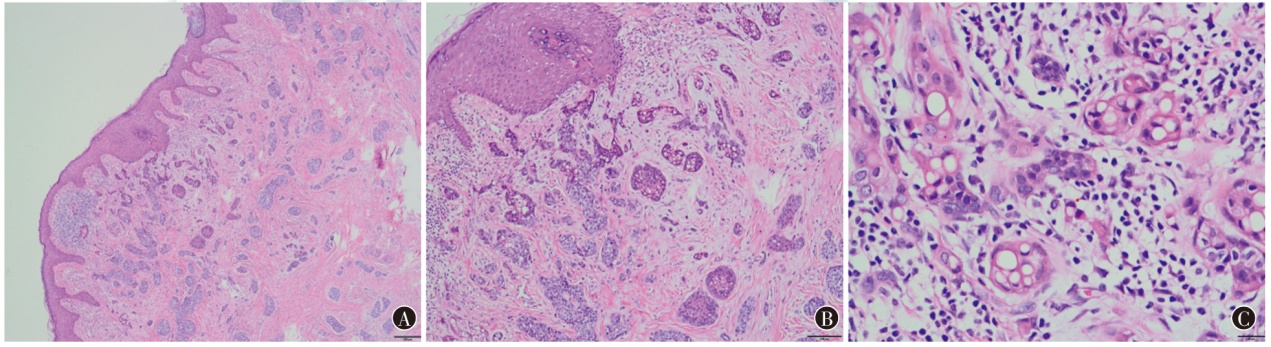

小汗腺汗孔癌(EPC)又称外泌汗腺汗孔癌,是一种少见的皮肤附属器恶性肿瘤,通常起源于小汗腺的导管,好发于头颈部和四肢皮肤,发生在乳头部位的较为罕见。现报道1例左乳头EPC患者的诊疗过程,复习相关文献并讨论,以期为临床提供诊疗思路。